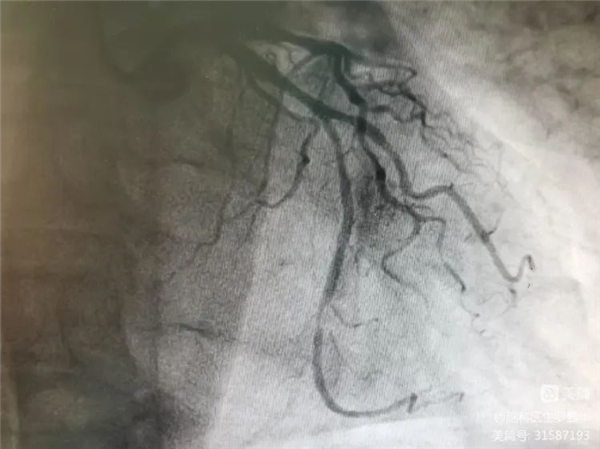

冠脈造影證實(shí)左旋支重度狹窄Xbg安康新聞網(wǎng)